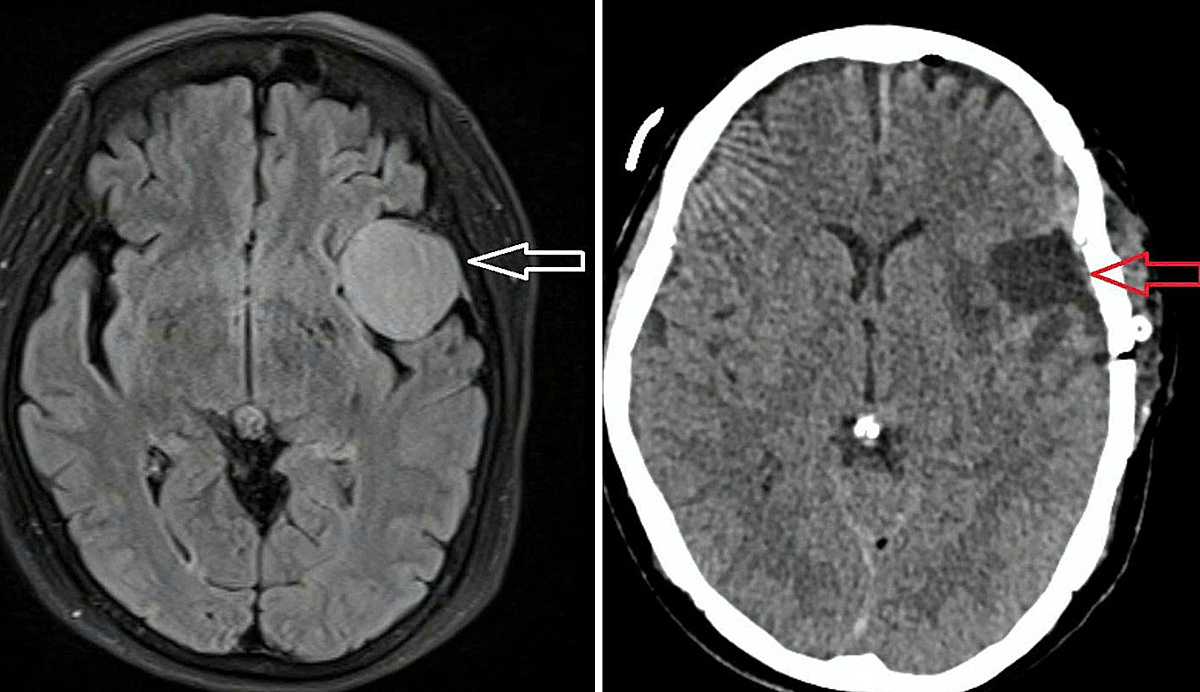

On 4/9, Doctor Truong Long Vy, head of neurosurgery at Thu Duc General Hospital, reported that a CT and MRI scan revealed a 3.5x5 cm meningioma in the patient's left temporal lobe. The patient had several underlying conditions, including diabetes, hypertension, and coronary artery disease, which were not well-controlled. A multidisciplinary team of doctors coordinated preoperative treatment, including discontinuing anticoagulants 5 days prior to the procedure.

The patient's brain tumor before (left) and after (right) surgery. Photo: Hospital provided

The surgical team utilized specialized equipment for cranial microsurgery, including a Mayo head frame, a surgical microscope, and a high-speed drill. The lengthy operation presented difficulties due to the thick dura mater adhering to the skull. The surgeons successfully removed the entire tumor without damaging surrounding structures.